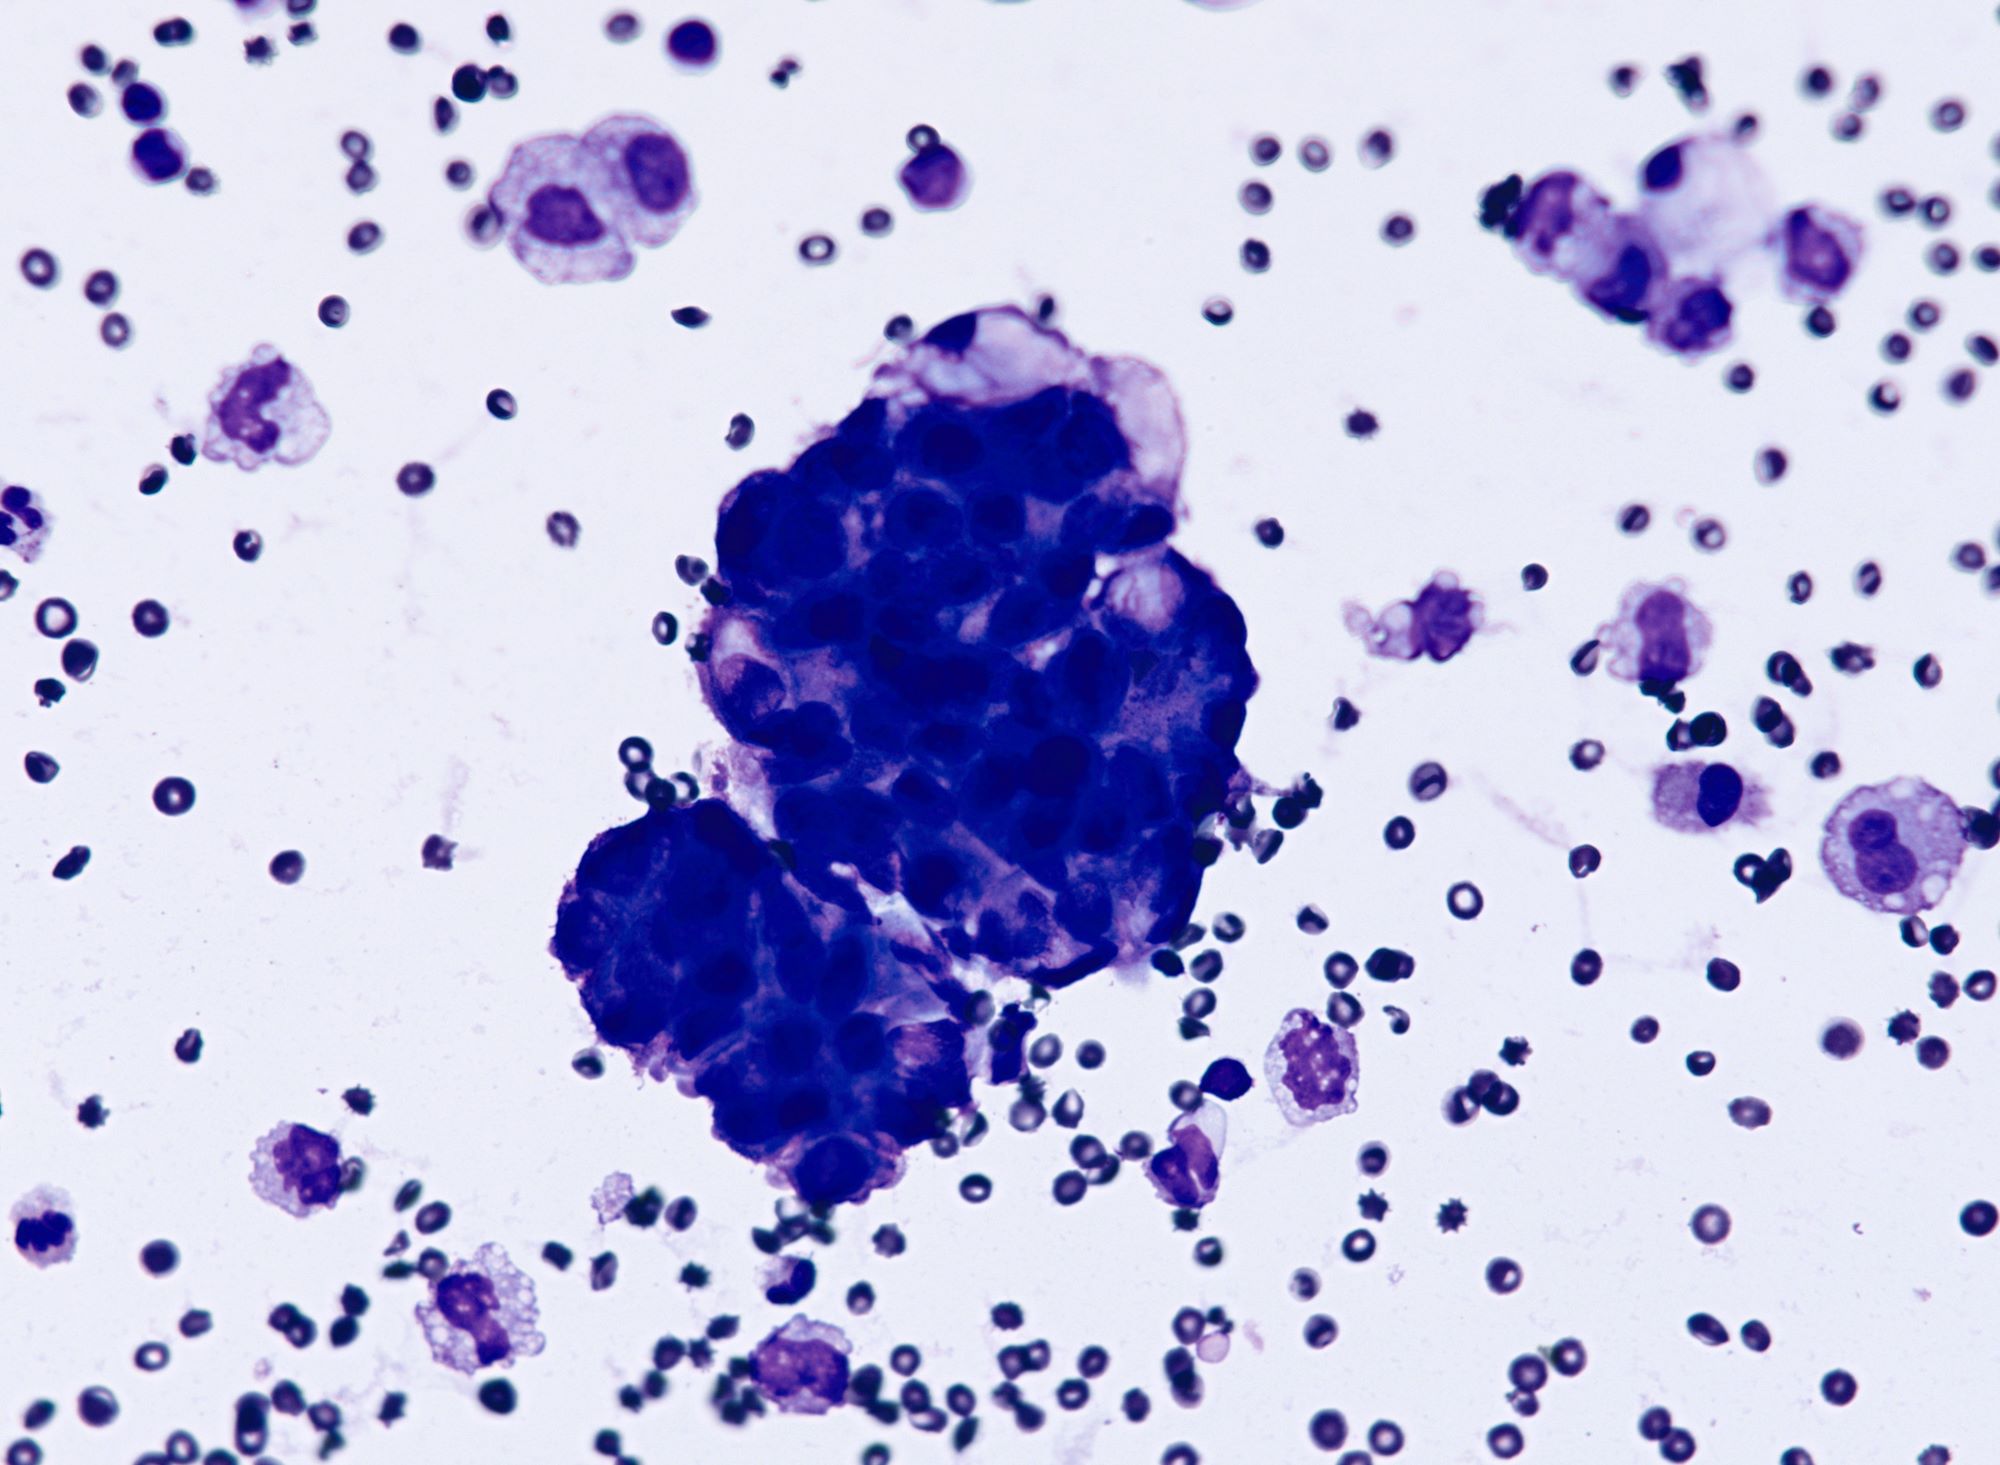

Cytology description

- Malignant glandular cells in clusters and singly

- Moderate amounts of finely vacuolated cytoplasm

- Enlarged hyperchromatic nuclei

- No significant nuclear pleomorphism (< 3x variation in size)

- Prominent nucleoli

Cytology images